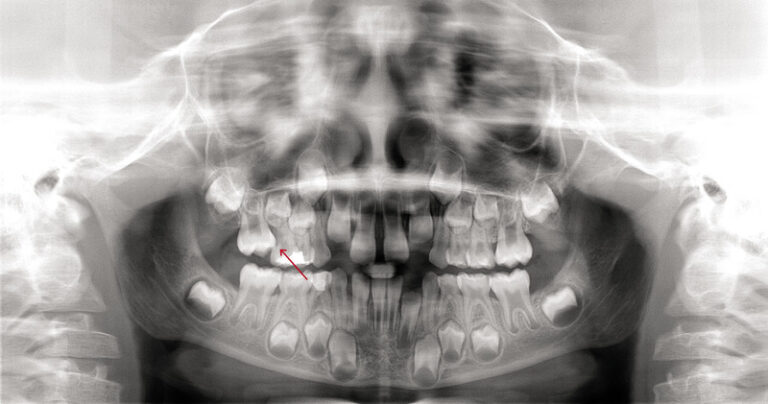

Czym jest elektrokoagulacja? Elektrokoagulacja to zabieg polegający na kontrolowanym wykorzystaniu prądu elektrycznego w celu zamknięcia naczyń krwionośnych oraz usunięcia zmienionych tkanek. W stomatologii metoda ta znajduje zastosowanie przede wszystkim w chirurgii i periodontologii. Stomatolog w nowoczesnej klinika stomatologiczna Kraków wykorzystuje…